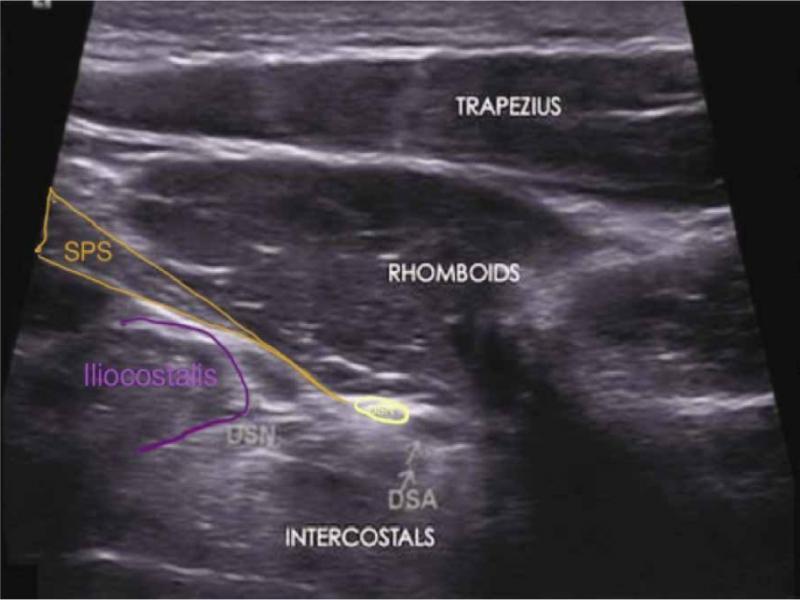

Fig. 1.

Proposed correct sonoanatomical locations of the dorsoscapular nerve (DSN) medial to the dorsoscapular artery (DSA) and posterolateral to the serratus posterior superior (SPS)

In Fig. 1B of Sharma’s manuscript, the linear muscle anterior to the rhomboids, posterior to the other paraspinal muscles, and with the muscle fibers directly slanting across the image, should be the serratus posterior superior (SPS) muscle. (Fig. 1) The DSN runs down the medial border of the scapula, deep to the levator scapulae and rhomboids, and superficial to the serratus anterior muscle and the SPS(24). However, the label of the DSN has been placed anterior to the SPS. Anatomically, this hypoechoic echostructure, considering it to be a swollen nerve, should be the posterior ramus of the thoracic spinal nerve, which is commonly entrapped by the insertion of the SPS over the second to fifth ribs. If this was swollen posterior ramus of the thoracic spinal nerve, the diagnosis in the case report should have been notalgia paresthetica (NP), which is attributed to the entrapment of the T2–T6 posterior rami that supply cutaneous innervation to the area(5). Additionally, the patient was treated with ultrasound-guided hydrodissection of the lateral branch of the posterior ramus of the thoracic spinal nerve. Herein, we provide a picture (Fig. 2) showing the sonoanatomy of the DSN in relation to the SPS, levator scapulae (LS), rhomboid minor (RMi), rhomboid major (RMa), and the levels from the second rib to the fifth rib. We also provide a video showing the scanning of these structures in Video 1.